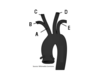

What compartment is A?

Vertebral compartment

What compartment is B?

Musculofascial collar

What compartment is C?

Vascular compartment

What compartment is D?

Visceral compartment